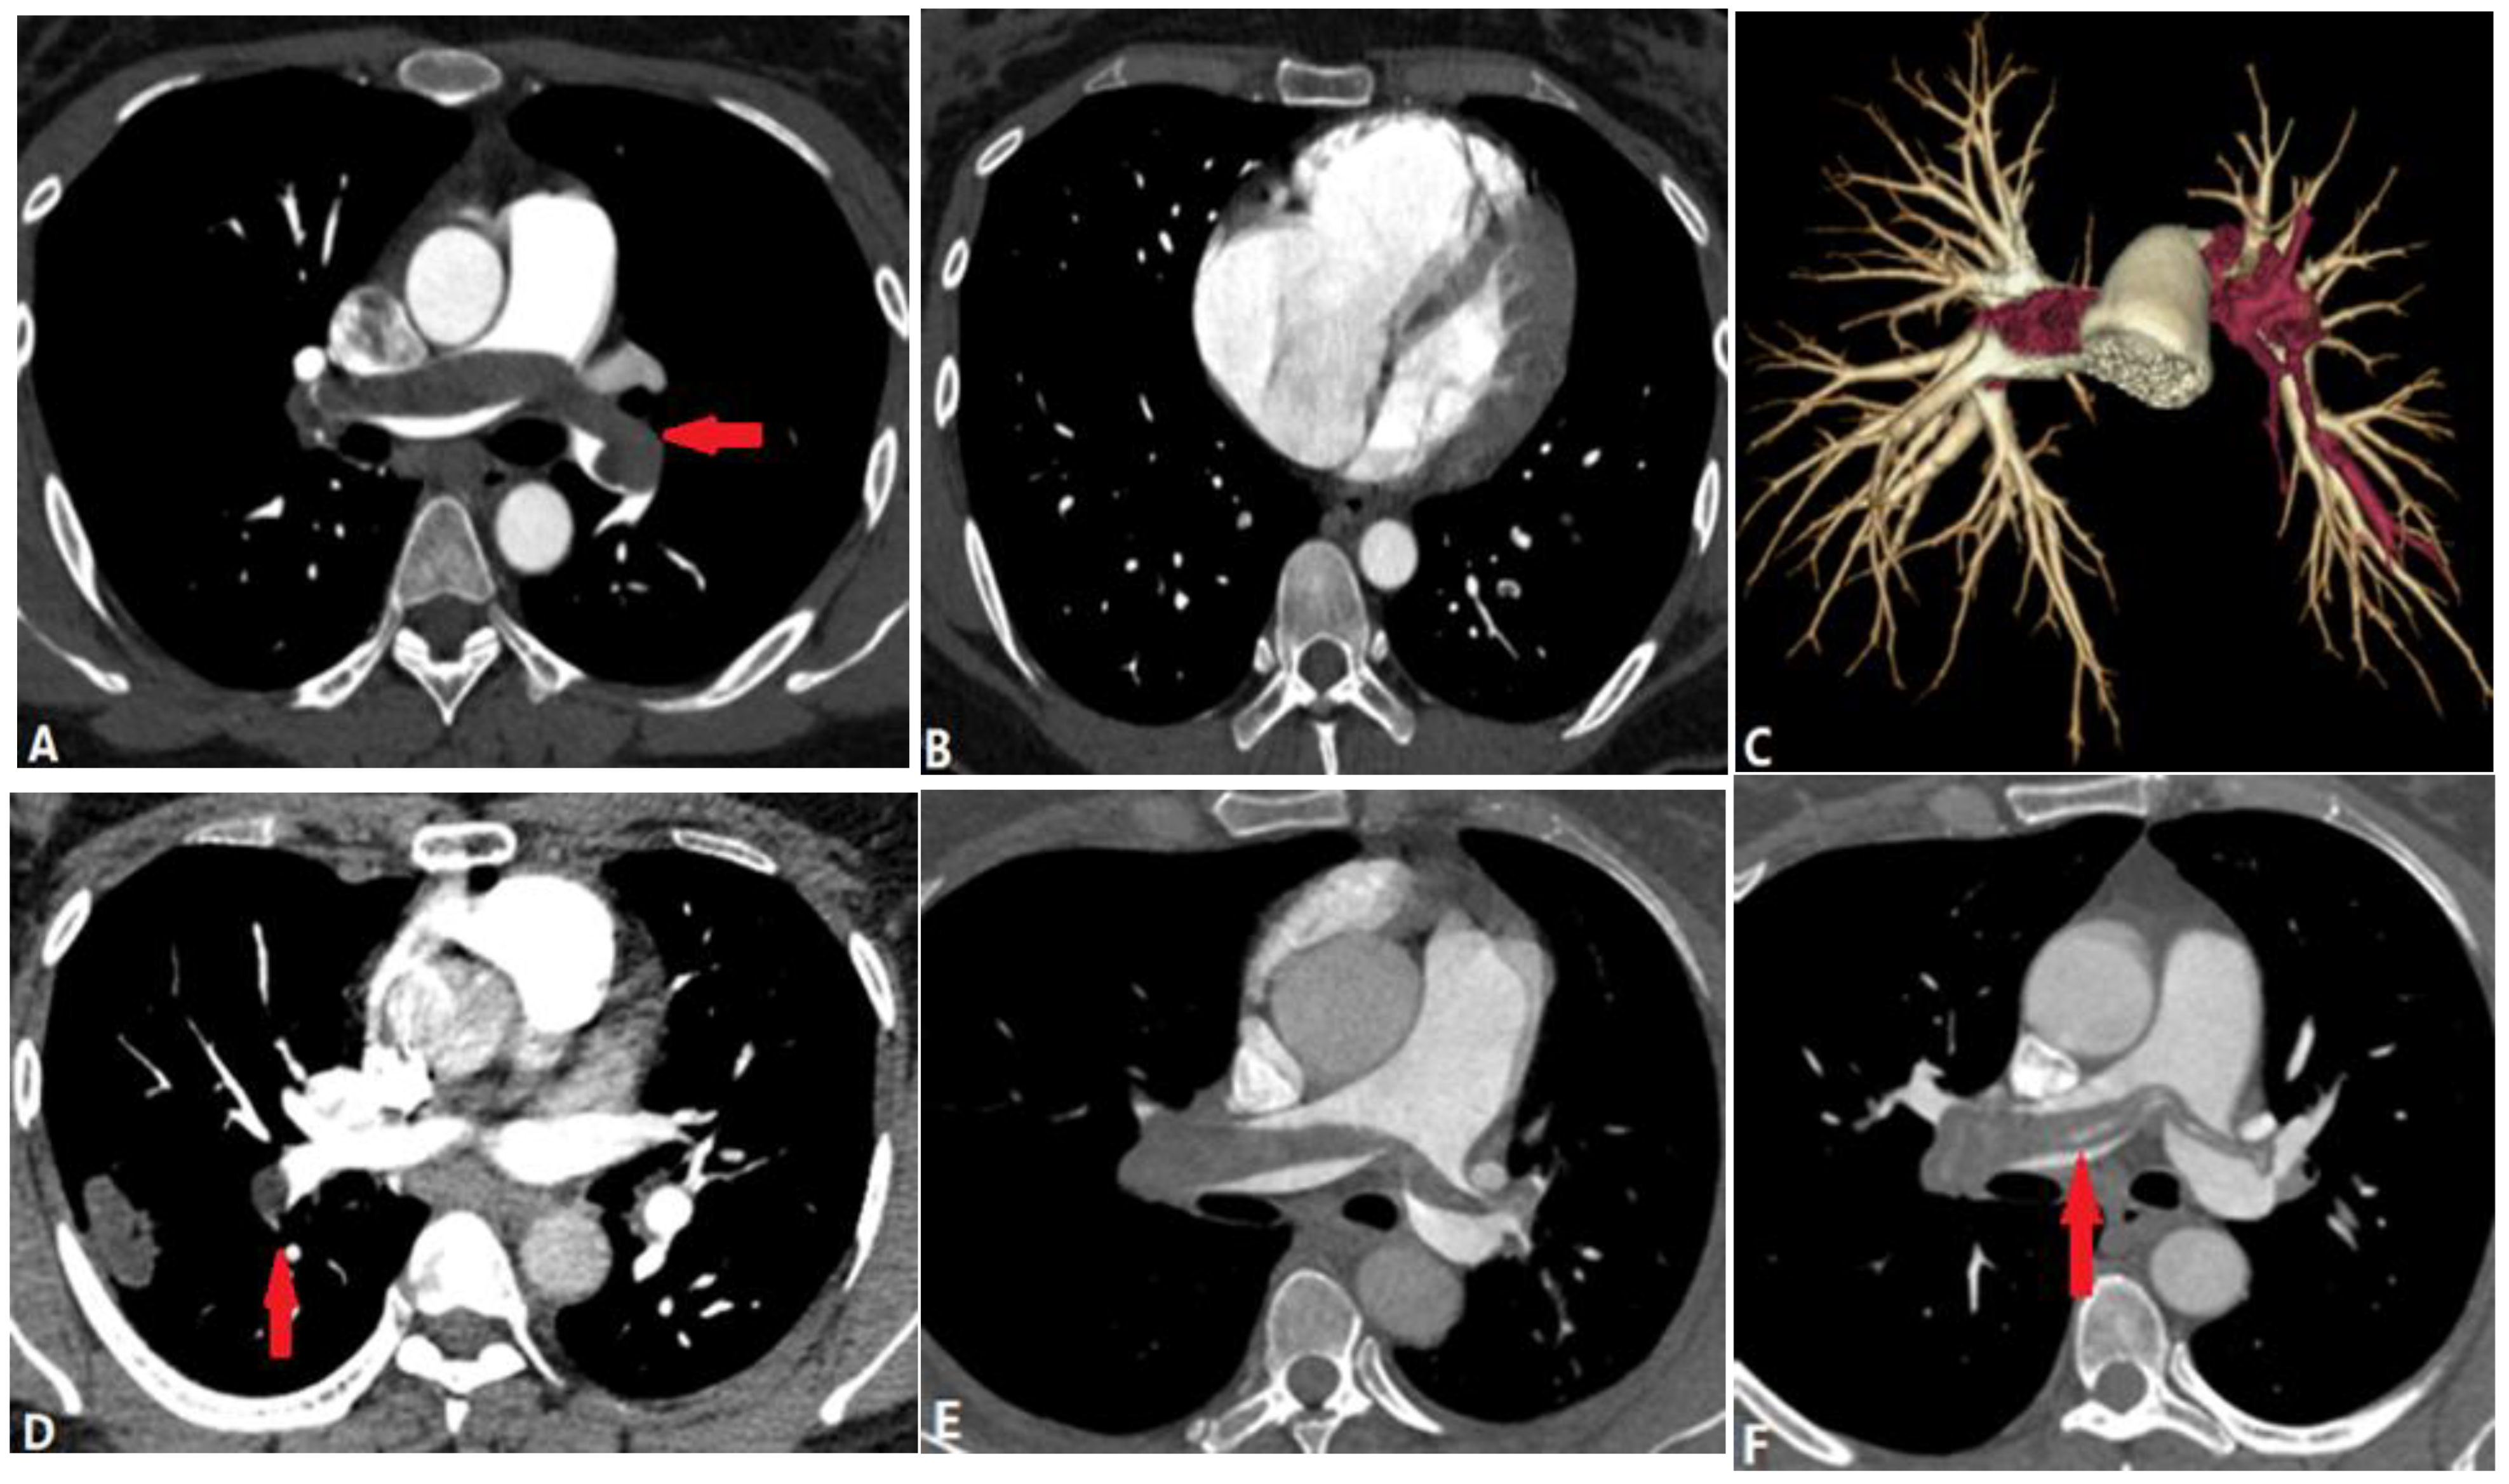

4.1.1. Pulmonary Thromboembolism (PTE)

4.1.2. In Situ Pulmonary Artery Thrombosis (PAT)

4.1.3. Pulmonary Tumor Embolism and Pulmonary Tumor Thrombotic Microangiography (PTTM)

4.1.4. Septic Pulmonary Embolism (SPE)

4.1.5. Pulmonary Embolism Caused by Foreign Bodies

4.1.6. Pulmonary Artery Sarcoma